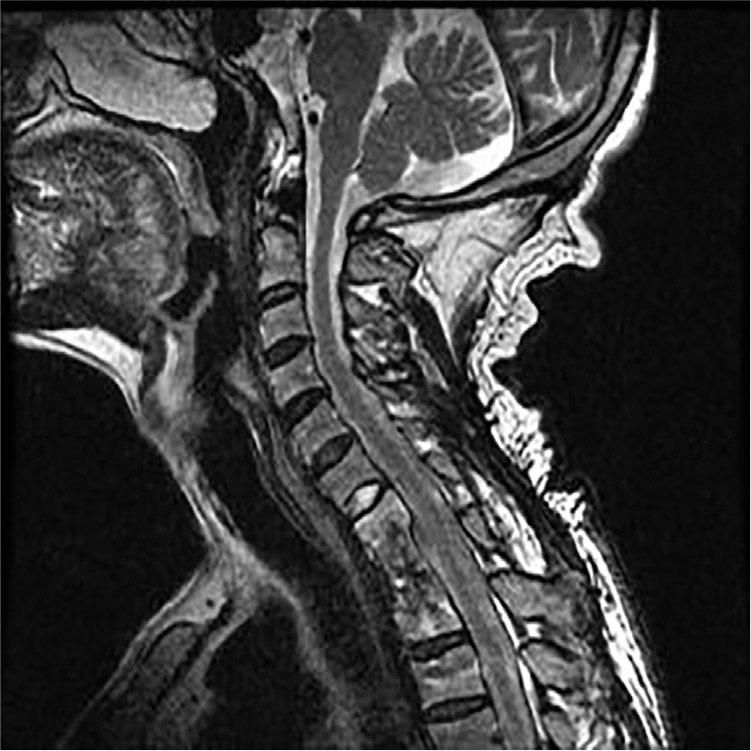

Figure 4

MR reexamination result of the thoracic vertebra after the operation.